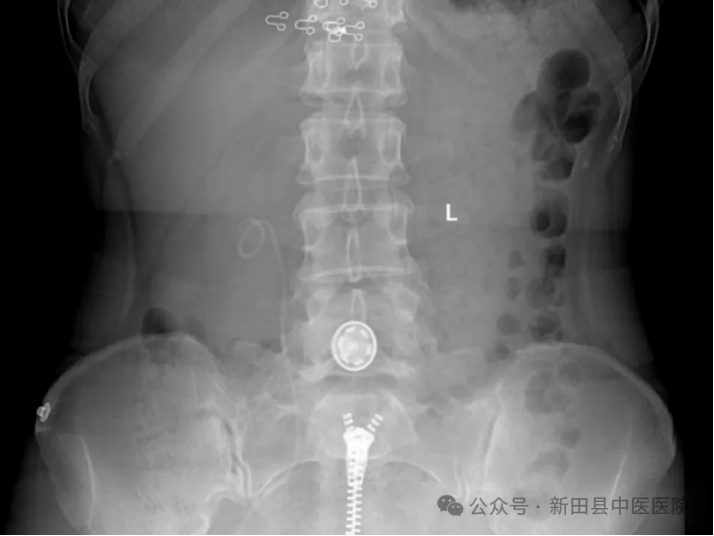

▲术前DR

▲术前CT